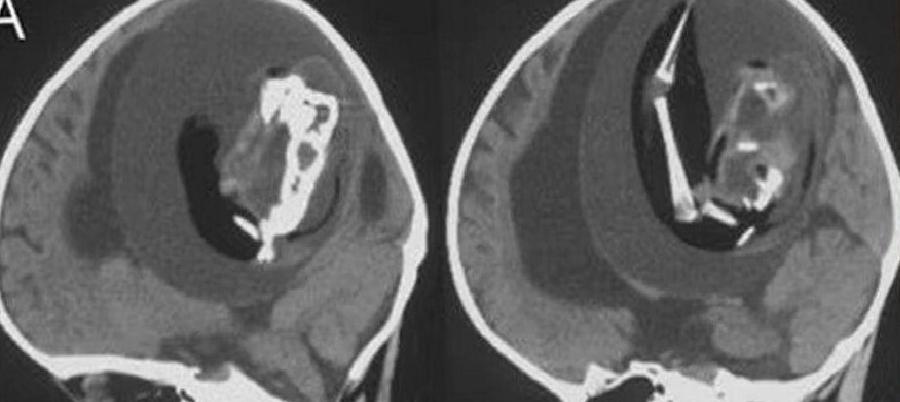

Aile, bebeklerinin motor becerilerinde yaşadığı sorunlar ve kafatasındaki aşırı büyüme nedeniyle hastaneye başvurdu. Yapılan MR görüntülemeleri, tıp camiasını şaşkına çevirdi. Bebeklerinin kafasında kemiksi bir yapı tespit edildi ve detaylı incelemeler sonucunda, bu yapının aslında gelişimini tamamlayamamış bir fetüs olduğu belirlendi.

Bebeğin durumu üzerine hemen ameliyat kararı alındı. Doktorların tüm çabalarına rağmen, 1 yaşındaki bebek kurtarılamadı. Ameliyat sırasında bebeğin kafasından; omurgası, gözleri, ağzı ve kolları gibi birçok organı gelişmiş bir fetüs çıkarıldı.